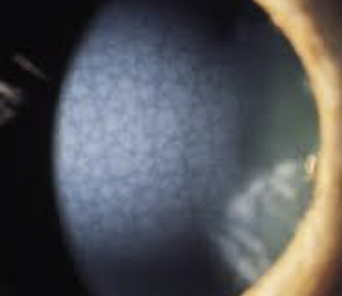

Fuchs endothelial dystrophy: inc in post lamina production causing guttata on BM of endo. This results in dec endo cell (<500 cells/mm2) resulting in stomal edema. Female over 60

Symptoms. blurred/hazy vision. Early signs are glare/light sensitivity. Late signs: pain/edema

Objective: Guttata starting 20-30s, early cataract, inc irsk for POAG, >600 pachymetry. May have bullae or RCE

Plan: Hypertonic 5% NaFl drops and ung at night. Bandage SCL if bullae or RCE.